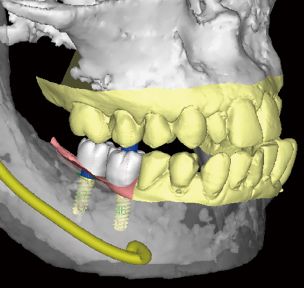

CT画像による診断

CTデータを実際の口腔内模型と合成し、インプラント埋入のシミュレーションを行います。